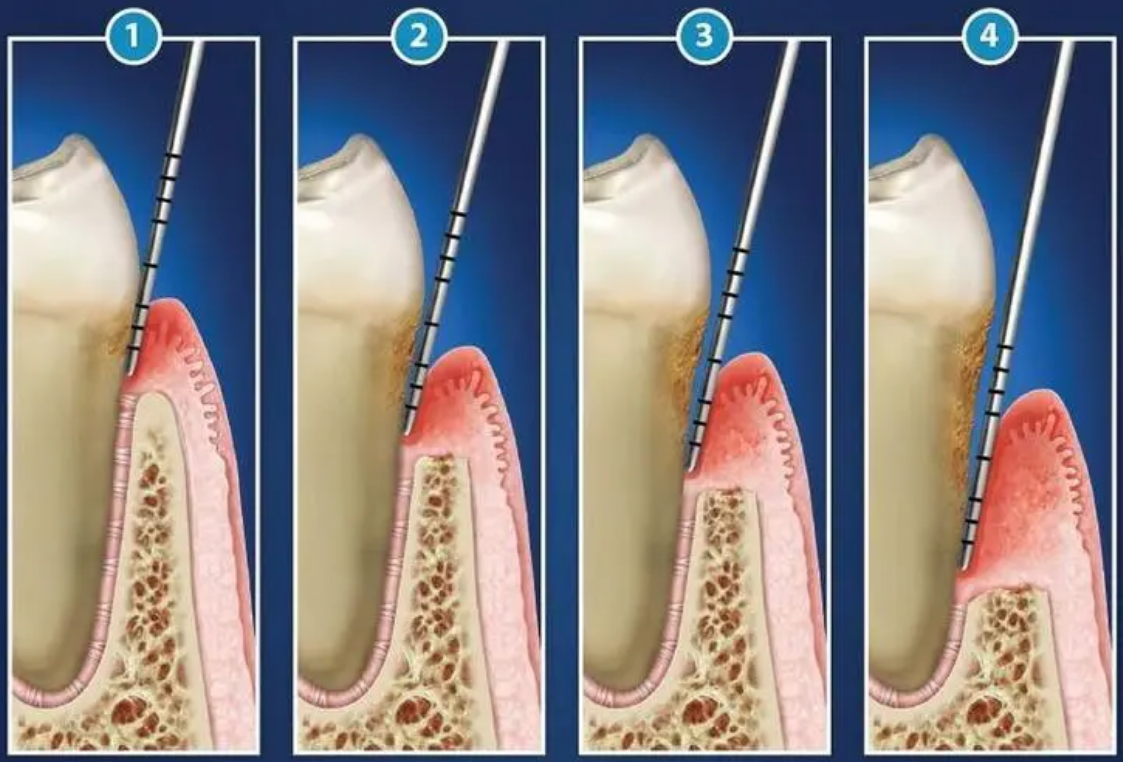

維港口腔醫生表示,當牙周袋深度超過3mm,表明存在重度牙周炎,呢種情況下,牙齒周圍嘅骨頭可能受到損害,導致牙齒逐漸松動。牙周炎嘅發展也意味着牙結石和牙菌斑已深入牙周組織。僅僅通過洗牙難以解決問題,因此醫生通常建議進行齦下刮治。然而,是否需要進行齦下刮治需要通過醫院拍片嚟評估,醫生會根據牙齒嘅具體情況決定合適嘅治療方式。

通常嚟講,進行齦下刮治系喺齦上潔治結束後嘅一周。齦下刮治相對較為刺激,通常需要喺局麻下使用超聲波手動刮治器深入牙齦根部,清除牙結石。刮治前會使用局部麻醉嚟減輕疼痛感,但由於牙齦十分敏感,喺刮治過程中可能仲有少少唔舒服,不過唔使過分擔心。